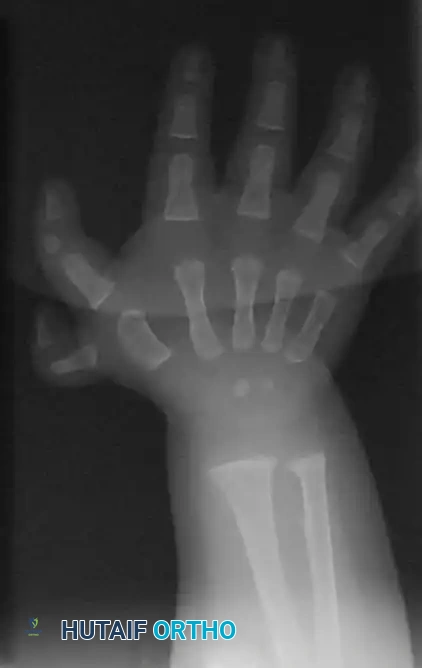

Technique 76-26: Excision and Reconstruction (Lamb, Marks, and Bayne) (For Types III through VI)

For asymmetrical duplications (the vast majority of cases), preservation of the dominant ulnar thumb with transfer of the radial structures is the gold standard.

Preoperative surgical markings outlining the racquet-shaped incision designed to excise the hypoplastic radial duplicate while preserving local skin flaps for tension-free closure.

Surgical Steps:

1. Incision: Under tourniquet control, make a racquet-shaped incision over the most hypoplastic thumb (typically the radialmost digit).

2. Intrinsic Tendon Preservation: Carefully dissect and identify the abductor pollicis brevis (APB) tendon as it inserts into the proximal phalanx of the radial duplicate. Detach it with a generous sleeve of periosteum for later transfer.

3. Ligamentous Dissection: Detach the radial collateral ligament (RCL) distally from the phalanx to be excised. Strip the RCL proximally off the metacarpal or phalanx, preserving it as a robust osteoperiosteal flap.

4. Ablation: Excise the supernumerary radial digit along with its corresponding articular facet.

5. Joint Contouring: If the metacarpal head is excessively broad or bifurcated, perform a longitudinal shaving osteotomy to narrow the articular surface, ensuring it matches the base of the preserved proximal phalanx.

6. Realignment and Fixation: Centralize the remaining ulnar digit over the newly contoured articular surface. Secure the alignment with a longitudinal K-wire driven retrograde across the joint.

7. Ligament and Tendon Reconstruction: Advance and suture the preserved RCL and the APB tendon securely to the radial base of the preserved proximal phalanx. This step is critical to prevent late ulnar deviation.

8. Tendon Centralization: Inspect the FPL and EPL tendons. If their insertion is eccentric, perform a partial resection, centralization, or transfer to ensure a perfectly central line of pull.

9. Closure: Close the skin with simple interrupted sutures. A Z-plasty may be required in the first web space or along the ulnar border to prevent scar contracture.

Post-ablation closure demonstrating meticulous skin approximation. Note the centralized alignment of the preserved ulnar digit.

Postoperative Protocol:

The thumb is immobilized in a cast for 4 weeks. Following K-wire removal, a custom thermoplastic protective splint is utilized for an additional 3 to 4 weeks during active play to protect the ligamentous reconstruction.